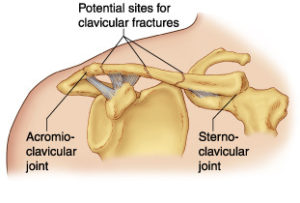

The Clavicle is part of your shoulder and connects your rib cage to your arm.

The Clavicle lies above several important nerves and blood vessels. However, these vital structures are rarely injured when the Clavicle breaks, even though the bone ends can shift when they are fractured.

The clavicle is a long bone and most breaks occur in the middle of it. Occasionally, the bone will break at its ends, where it attaches at the ribcage or Shoulder blade.